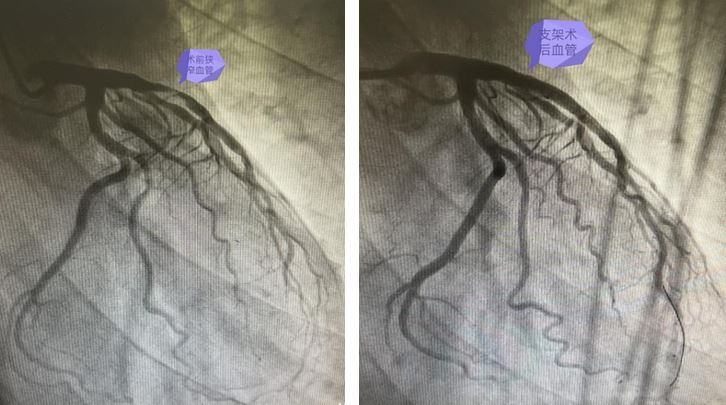

术前及术后病变血管

为患者行急诊PCI手术,冠脉造影术检查显示,前降支近中远段可见弥漫性狭窄,近中段可见血栓影存在,狭窄最重约95%,远段狭窄最重约40%,结合患者心电图表现,考虑前降支为本次发病罪犯血管,经评估后为患者行冠状动脉血栓抽吸术,回抽可见血栓存在,血栓抽吸完毕后顺利为患者在病变处串联植入支架2枚,复查造影结果显示支架贴壁良好,未见明显贴壁不良。